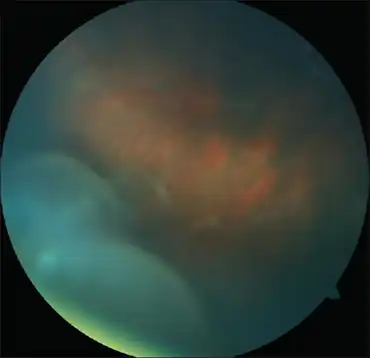

Anterior vitreous cells in Intermediate uveitis | |

Intermediate uveitis is a form of uveitis localized to the vitreous and peripheral retina. Primary sites of inflammation include the vitreous of which other such entities as pars planitis, posterior cyclitis, and hyalitis are encompassed. Intermediate uveitis may either be an isolated eye disease or associated with the development of a systemic disease such as multiple sclerosis or sarcoidosis. As such, intermediate uveitis may be the first expression of a systemic condition. Infectious causes of intermediate uveitis include Epstein-Barr virus infection, Lyme disease, HTLV-1 virus infection, cat scratch disease, and hepatitis C.